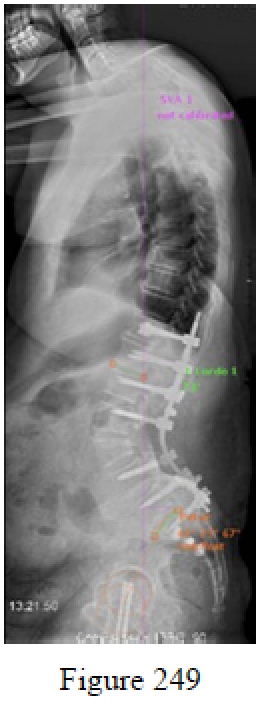

Question 249

Figure 249 is the standing lateral radiograph of a 69-year-old woman who underwent a 3-column osteotomy and posterior thoracolumbar fusion to correct a sagittal plane deformity. Which risk factor is associated with the highest incidence of a major perioperative complication?